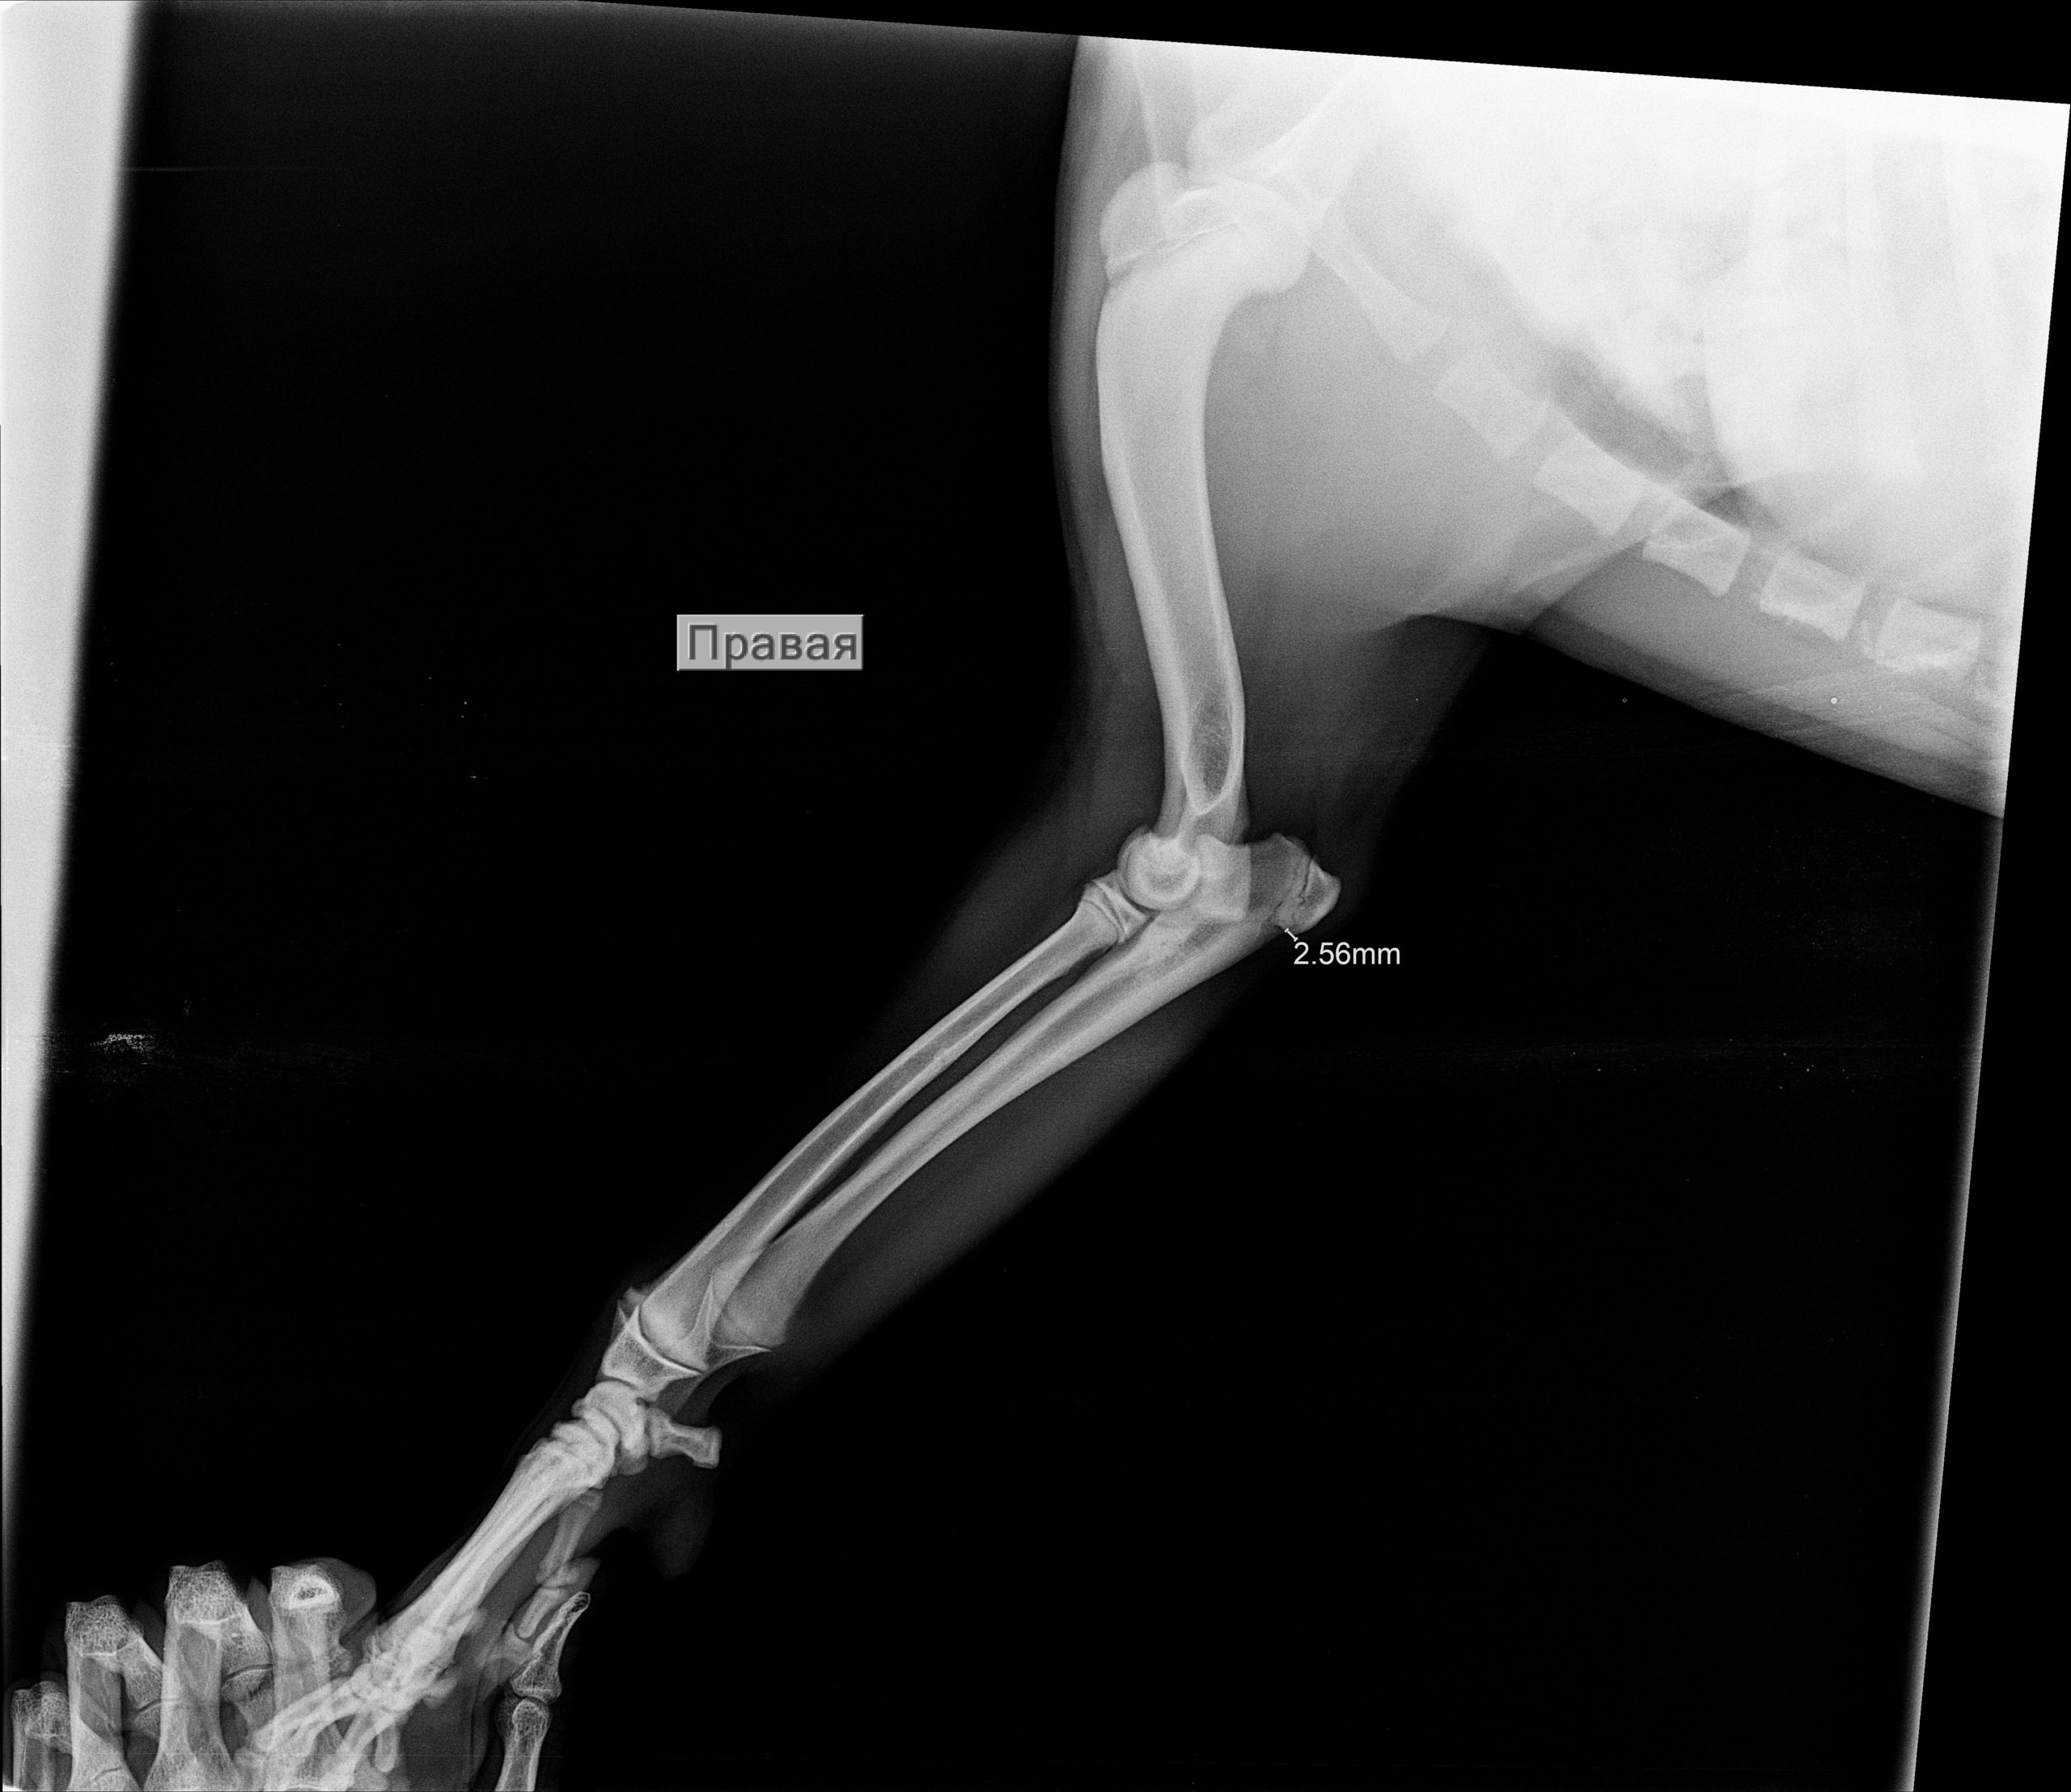

Рентген Задней Лапы Кошки: Нормы и Диагностика